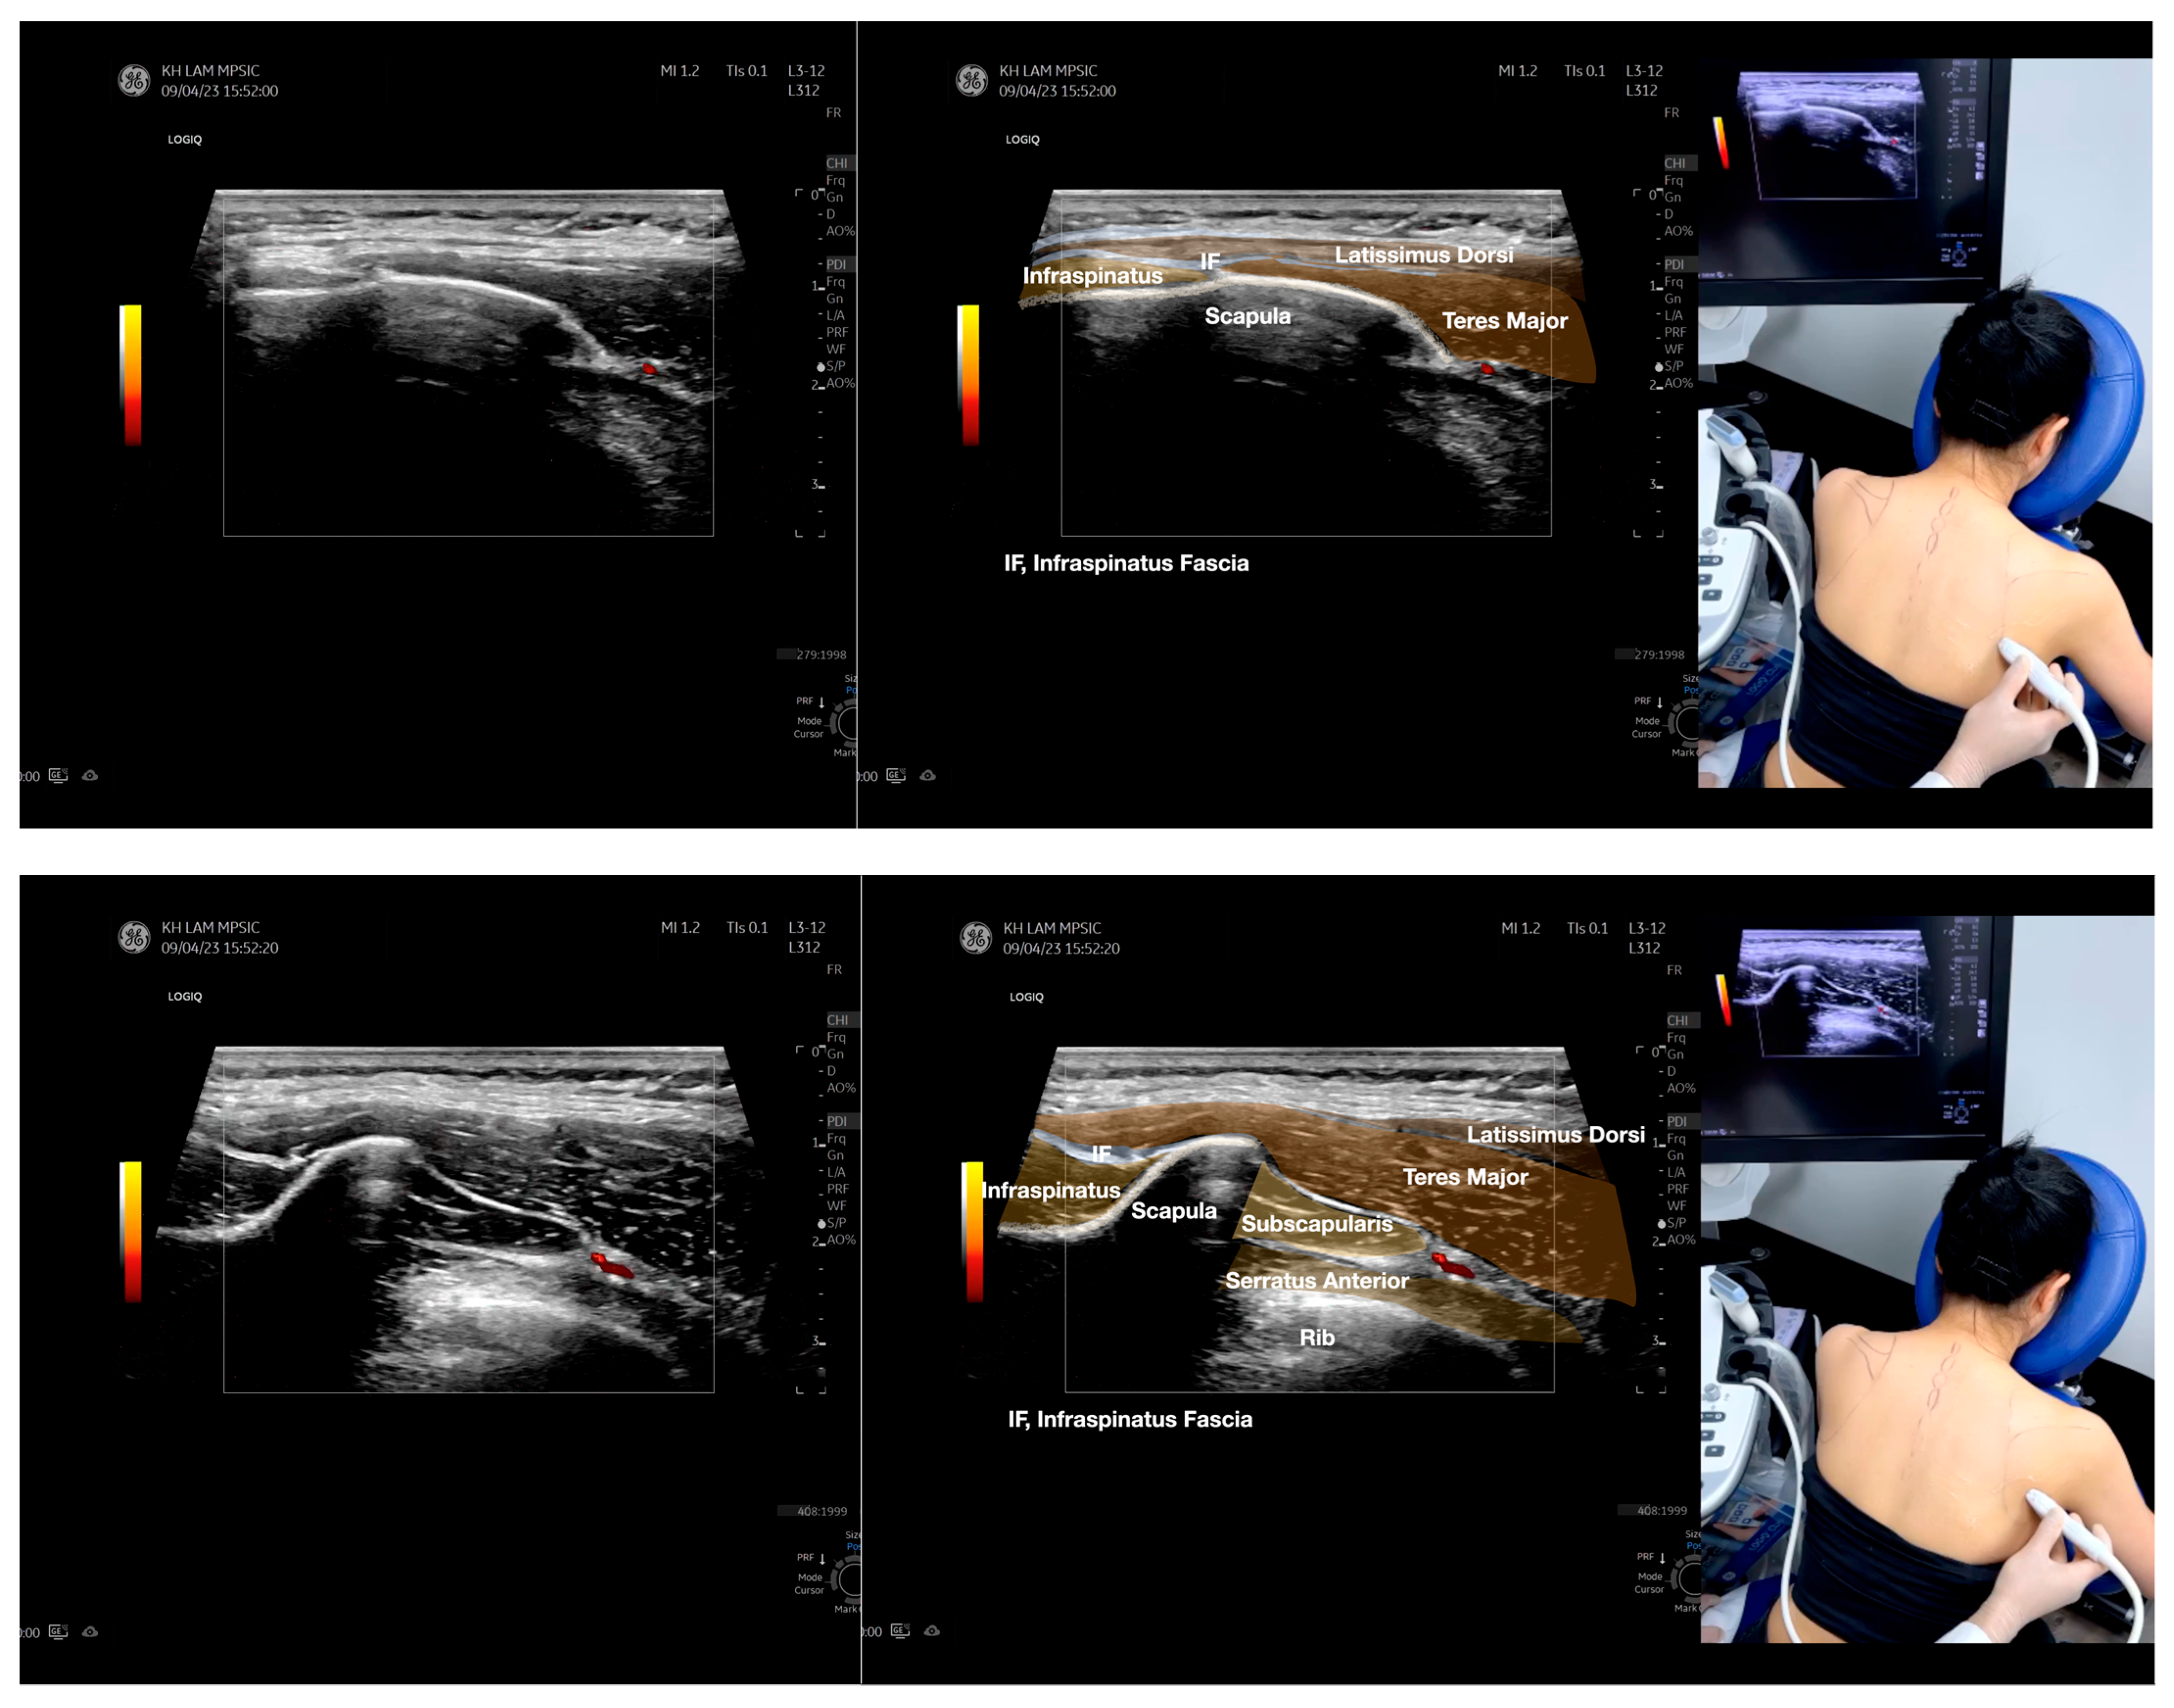

Figure 5.

Sonoanatomy of scanning the infraspinatus fascia in the sagittal plane from the rhomboid minor laterally, then back to the rhomboid major. The step-by-step scanning techniques of the structures illustrated in this figure have been shown in Video S9. Available online: https://www.dropbox.com/s/gu9hhrdq9erin6n/Figure%205.docx?dl=0 (accessed on 1 January 2023).